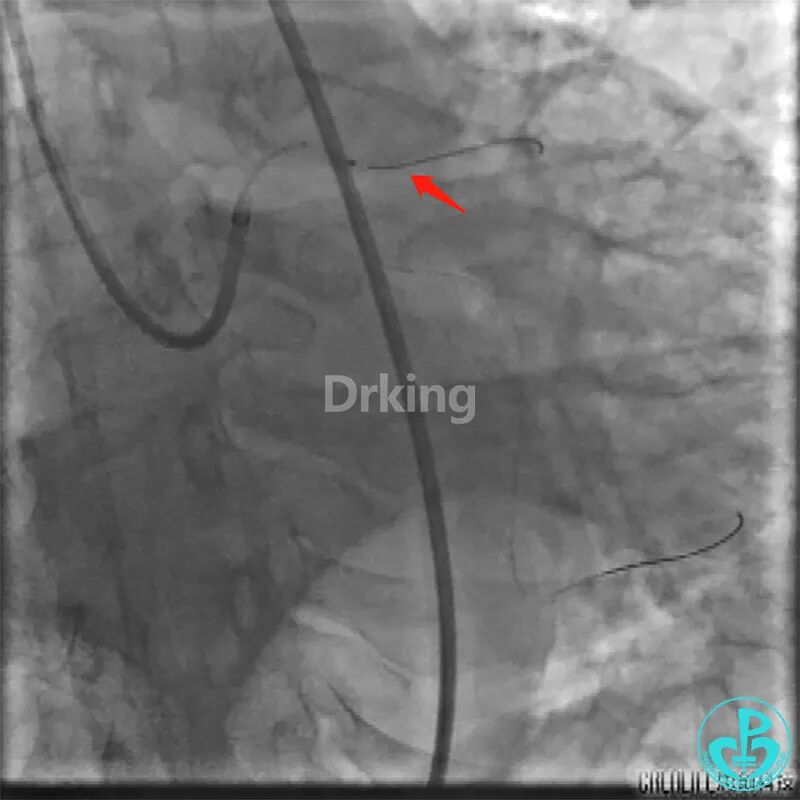

该患者于2019年03月28日在外院(县级市医院和地区级医学院附属大医院)两次冠脉造影术及PCI治疗均没成功,过程如下:

该患者近日转诊到江苏省人民医院,复查冠脉造影术,提示LCX近段扭曲严重(2处90度扭曲)的远段95%狭窄。当地医院市级及地区级医学院附属医院曾反复尝试,导丝均未能通过LCX近段扭曲处送至远段。